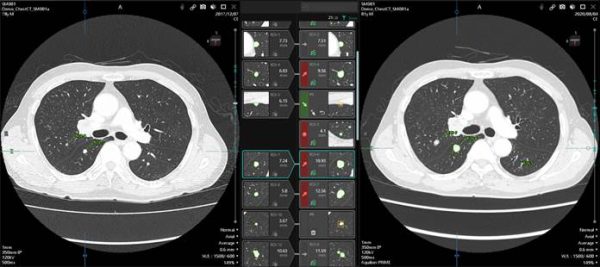

最先端AIで支援するPACS読影「Abierto Reading Support Solution」

ぎごちないワークフローで研究的にAIを試行する時代はすでに去った。医療のタスクシフトや医師の働き方改革が本番を迎える昨今、日常診療におけるPACS読影の労役軽減の声がことのほか高まっている。読影者の負担を軽減しながら大量の画像を効率よく、しかし見逃しなく緻密に読影する。控えめながらも患者さんの生死をも左右しかねない重要な命題であり、ここに日々向き合う読影者の心理的・肉体的負担は計り知れない。

「Abierto Reading Support Solution」は、この命題に対するキヤノンの明確な解答である。

誰にでもわかりやすいビジュアルかつ直感的な操作インターフェイスは、特に比較読影時の負担を劇的に減らす。エビデンスに裏付けされた高精度な臨床AI解析技術が、迅速的確な臨床判断を強力にサポートしてくれる。「Abierto Reading Support Solution」が日常臨床に与えるインパクトは大きい。